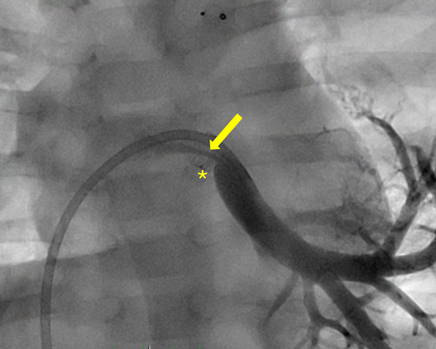

Figure 1. Frontal projection of a stented left lower pulmonary vein (*) with discrete distal stenosis (arrow) in an infant (5 mm x 8 mm Megatron DES).